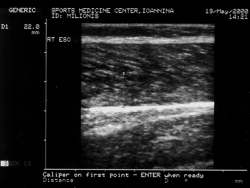

Υπέρηχοι

Η χρήση της υπερηχοτογραφίας για την απεικόνιση του μυοσκελετικού συστήματος αποτελεί μια μη επεμβατική μέθοδο η οποία δεν έχει παρενέργειες (δεν επιβαρύνει τον ασθενή με ιονίζουσα ακτινοβολία) και είναι ανεκτή από ομάδες ασθενών όπως παιδιά, κλειστοφοβικούς και με εμφυτεύματα στους οποίους η εξέταση με MRI ή CT είναι δυσχερής ή αντενδείκνεται. Επιπλέον, δίνει τη δυνατότητα στατικής και δυναμικής απεικόνισης, βοηθώντας τον ιατρό στην καλύτερη εκτίμηση της παθολογίας. Χρησιμοποιείται για την απεικόνιση μυών, τενόντων, συνδέσμων και σε ορισμένες περιπτώσεις οστών.

Συγκεκριμένα, η υπερηχοτογραφία χρησιμοποιείται ευρέως στην εκτίμηση παθήσεων του ώμου. Αναφέρεται ότι η ευαισθησία της μεθόδου στη διάγνωση ρήξης των στροφέων του ώμου (rotator cuff) είναι 67-100% και η ειδικότητα 85-100%. Επίσης αποτελεί σημαντικό διαγνωστικό μέσο των παθήσεων του αχίλλειου και του επιγονατιδικού τένοντα. Στην άρθρωση του γόνατος χρησιμοποιείται για τη διάγνωση και παρακολούθηση παθήσεων τενόντων και συνδέσμων, κύστης Baker ενώ υπάρχουν μελέτες και για τη χρήση της στη διάγνωση ρήξης μηνίσκων και προσθίου χιαστού συνδέσμου. Επίσης, σημαντικός είναι ο ρόλος της στη διάγνωση και παρακολούθηση παθήσεων και τραυματισμών των μυών.